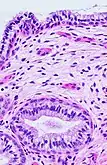

Transformation zone mucosa, when the squamocolumnar junction has a gradual transition. It consists of a mix of stratified squamous epithelium and mucinous glands. H&E stain.

Histology of endocervix, with mucinous columnar epithelium and mucinous glands. H&E stain.

The endocervical mucosa is about 3 mm (0.12 in) thick and lined with a single layer of columnar mucous cells. It contains numerous tubular mucous glands, which empty viscous alkaline mucus into the lumen.[4] In contrast, the ectocervix is covered with nonkeratinized stratified squamous epithelium,[4] which resembles the squamous epithelium lining the vagina.[17]:41 The junction between these two types of epithelia is called the squamocolumnar junction.[17]:408–11 Underlying both types of epithelium is a tough layer of collagen.[18] The mucosa of the endocervix is not shed during menstruation. The cervix has more fibrous tissue, including collagen and elastin, than the rest of the uterus.[4]

In prepubertal girls, the functional squamocolumnar junction is present just within the cervical canal.[17]:411 Upon entering puberty, due to hormonal influence, and during pregnancy, the columnar epithelium extends outward over the ectocervix as the cervix everts.[15]:106 Hence, this also causes the squamocolumnar junction to move outwards onto the vaginal portion of the cervix, where it is exposed to the acidic vaginal environment.[15]:106[17]:411 The exposed columnar epithelium can undergo physiological metaplasia and change to tougher metaplastic squamous epithelium in days or weeks,[17]:25 which is very similar to the original squamous epithelium when mature.[17]:411 The new squamocolumnar junction is therefore internal to the original squamocolumnar junction, and the zone of unstable epithelium between the two junctions is called the transformation zone of the cervix.[17]:411 Histologically, the transformation zone is generally defined as surface squamous epithelium with surface columnar epithelium or stromal glands/crypts, or both.[20]